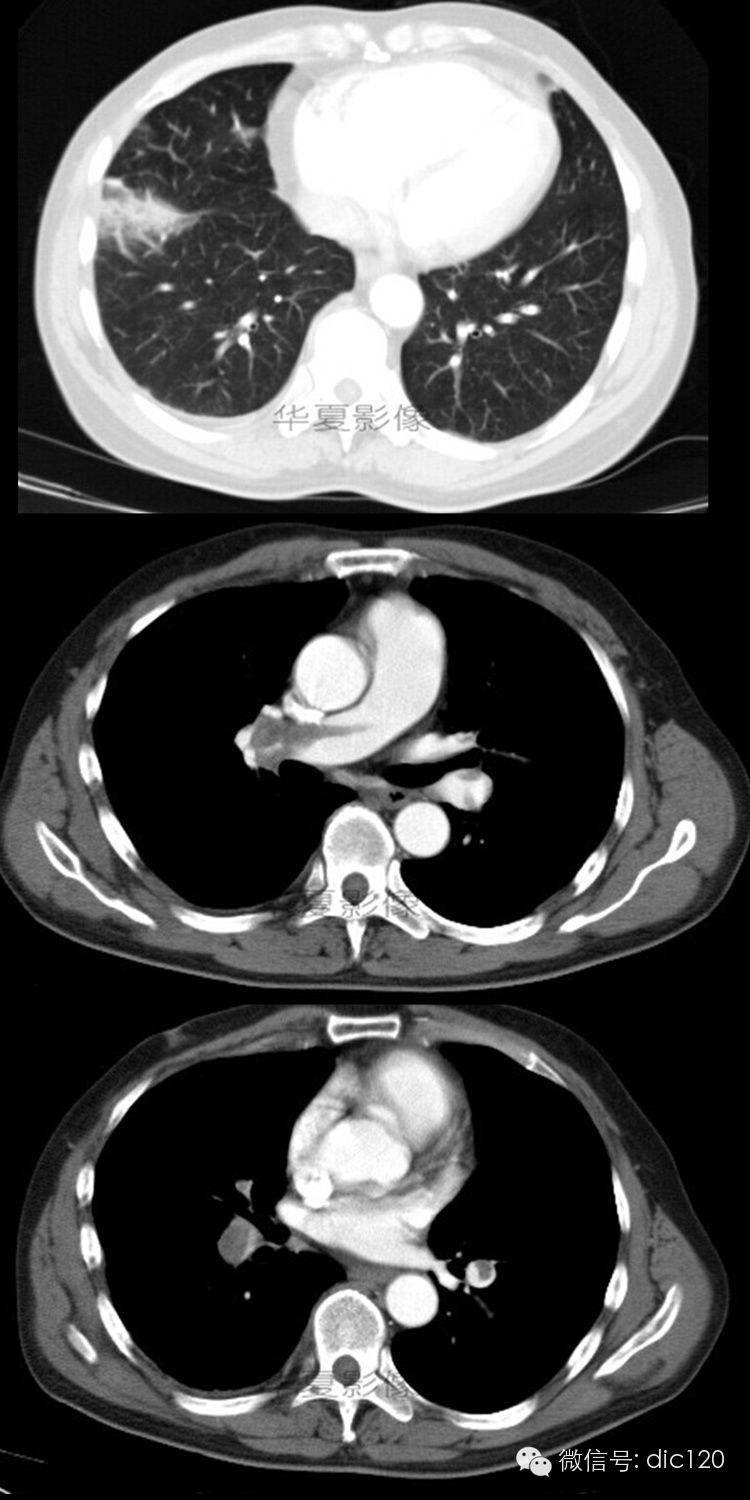

【病例】肺动脉栓塞并肺梗死1例CT影像表现

男,56岁;咳嗽、咳痰胸痛4天。

右肺下叶前基底段见胸膜下楔形高密度影,尖端指向肺门,部分边界清楚;增强后肺动脉及其各大分支内可见条带状无强化充盈缺损征。

诊断依据:典型影像表现,对症治疗后病灶明显缩小,部分消失;临床症状好转。

肺动脉内有栓子是诊断肺动脉栓塞最可靠的征象,增强后栓子不强化,栓子的形态和栓塞的程度不同,CT表现也各异。血栓位于血管腔中心呈长条状与血管腔平 行,当栓子与扫描层面平行,中央的栓子则呈条状低密度带,两边有含有对比剂的血流,二者形成鲜明的对比,即呈“轨道征”;栓塞的血管远端呈低密度而无对比 剂充盈,出现典型的“血管截断征”;血管腔一侧出现偏心性充盈缺损,对侧充盈高密度对比剂;当梗死灶形成后,表现为胸膜下楔形或片状软组织密度,尖端指向 肺门;有时还可以见到肺动脉高压和胸腔积液等征象。